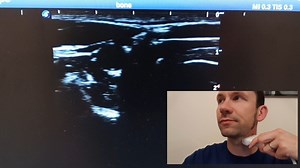

8. Blood Vessel Part 1 - Probe Posn & Inflate Jugs

2018年8月27日

Vimeo

TomWarrender